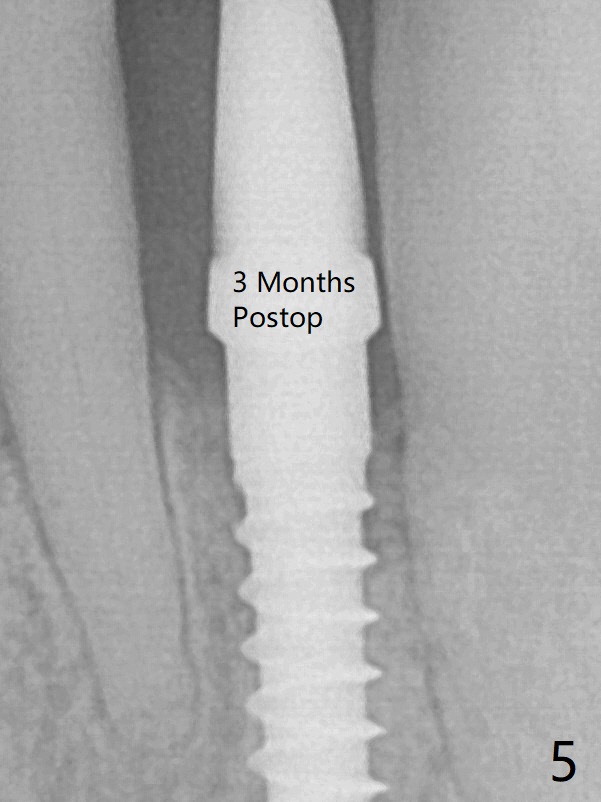

The gingival depth is measured 2-4 mm after extraction. The 1st intraop PA taken with 1.2 mm drill for 16 mm shows the mesiodistal width is 5.11 mm (Fig.2); a 2.5x14(2) mm 1-piece implant is placed with >35 Ncm (Fig.3 with allograft placed). There is no bone loss 3 months postop (Fig.5). The distal crest seems to be reduced in density and lower in height 1 year 7 months (Fig.7) and 1 year 11 months (Fig.8) post cementation. The severity does not worsen probably related to use of water pik.